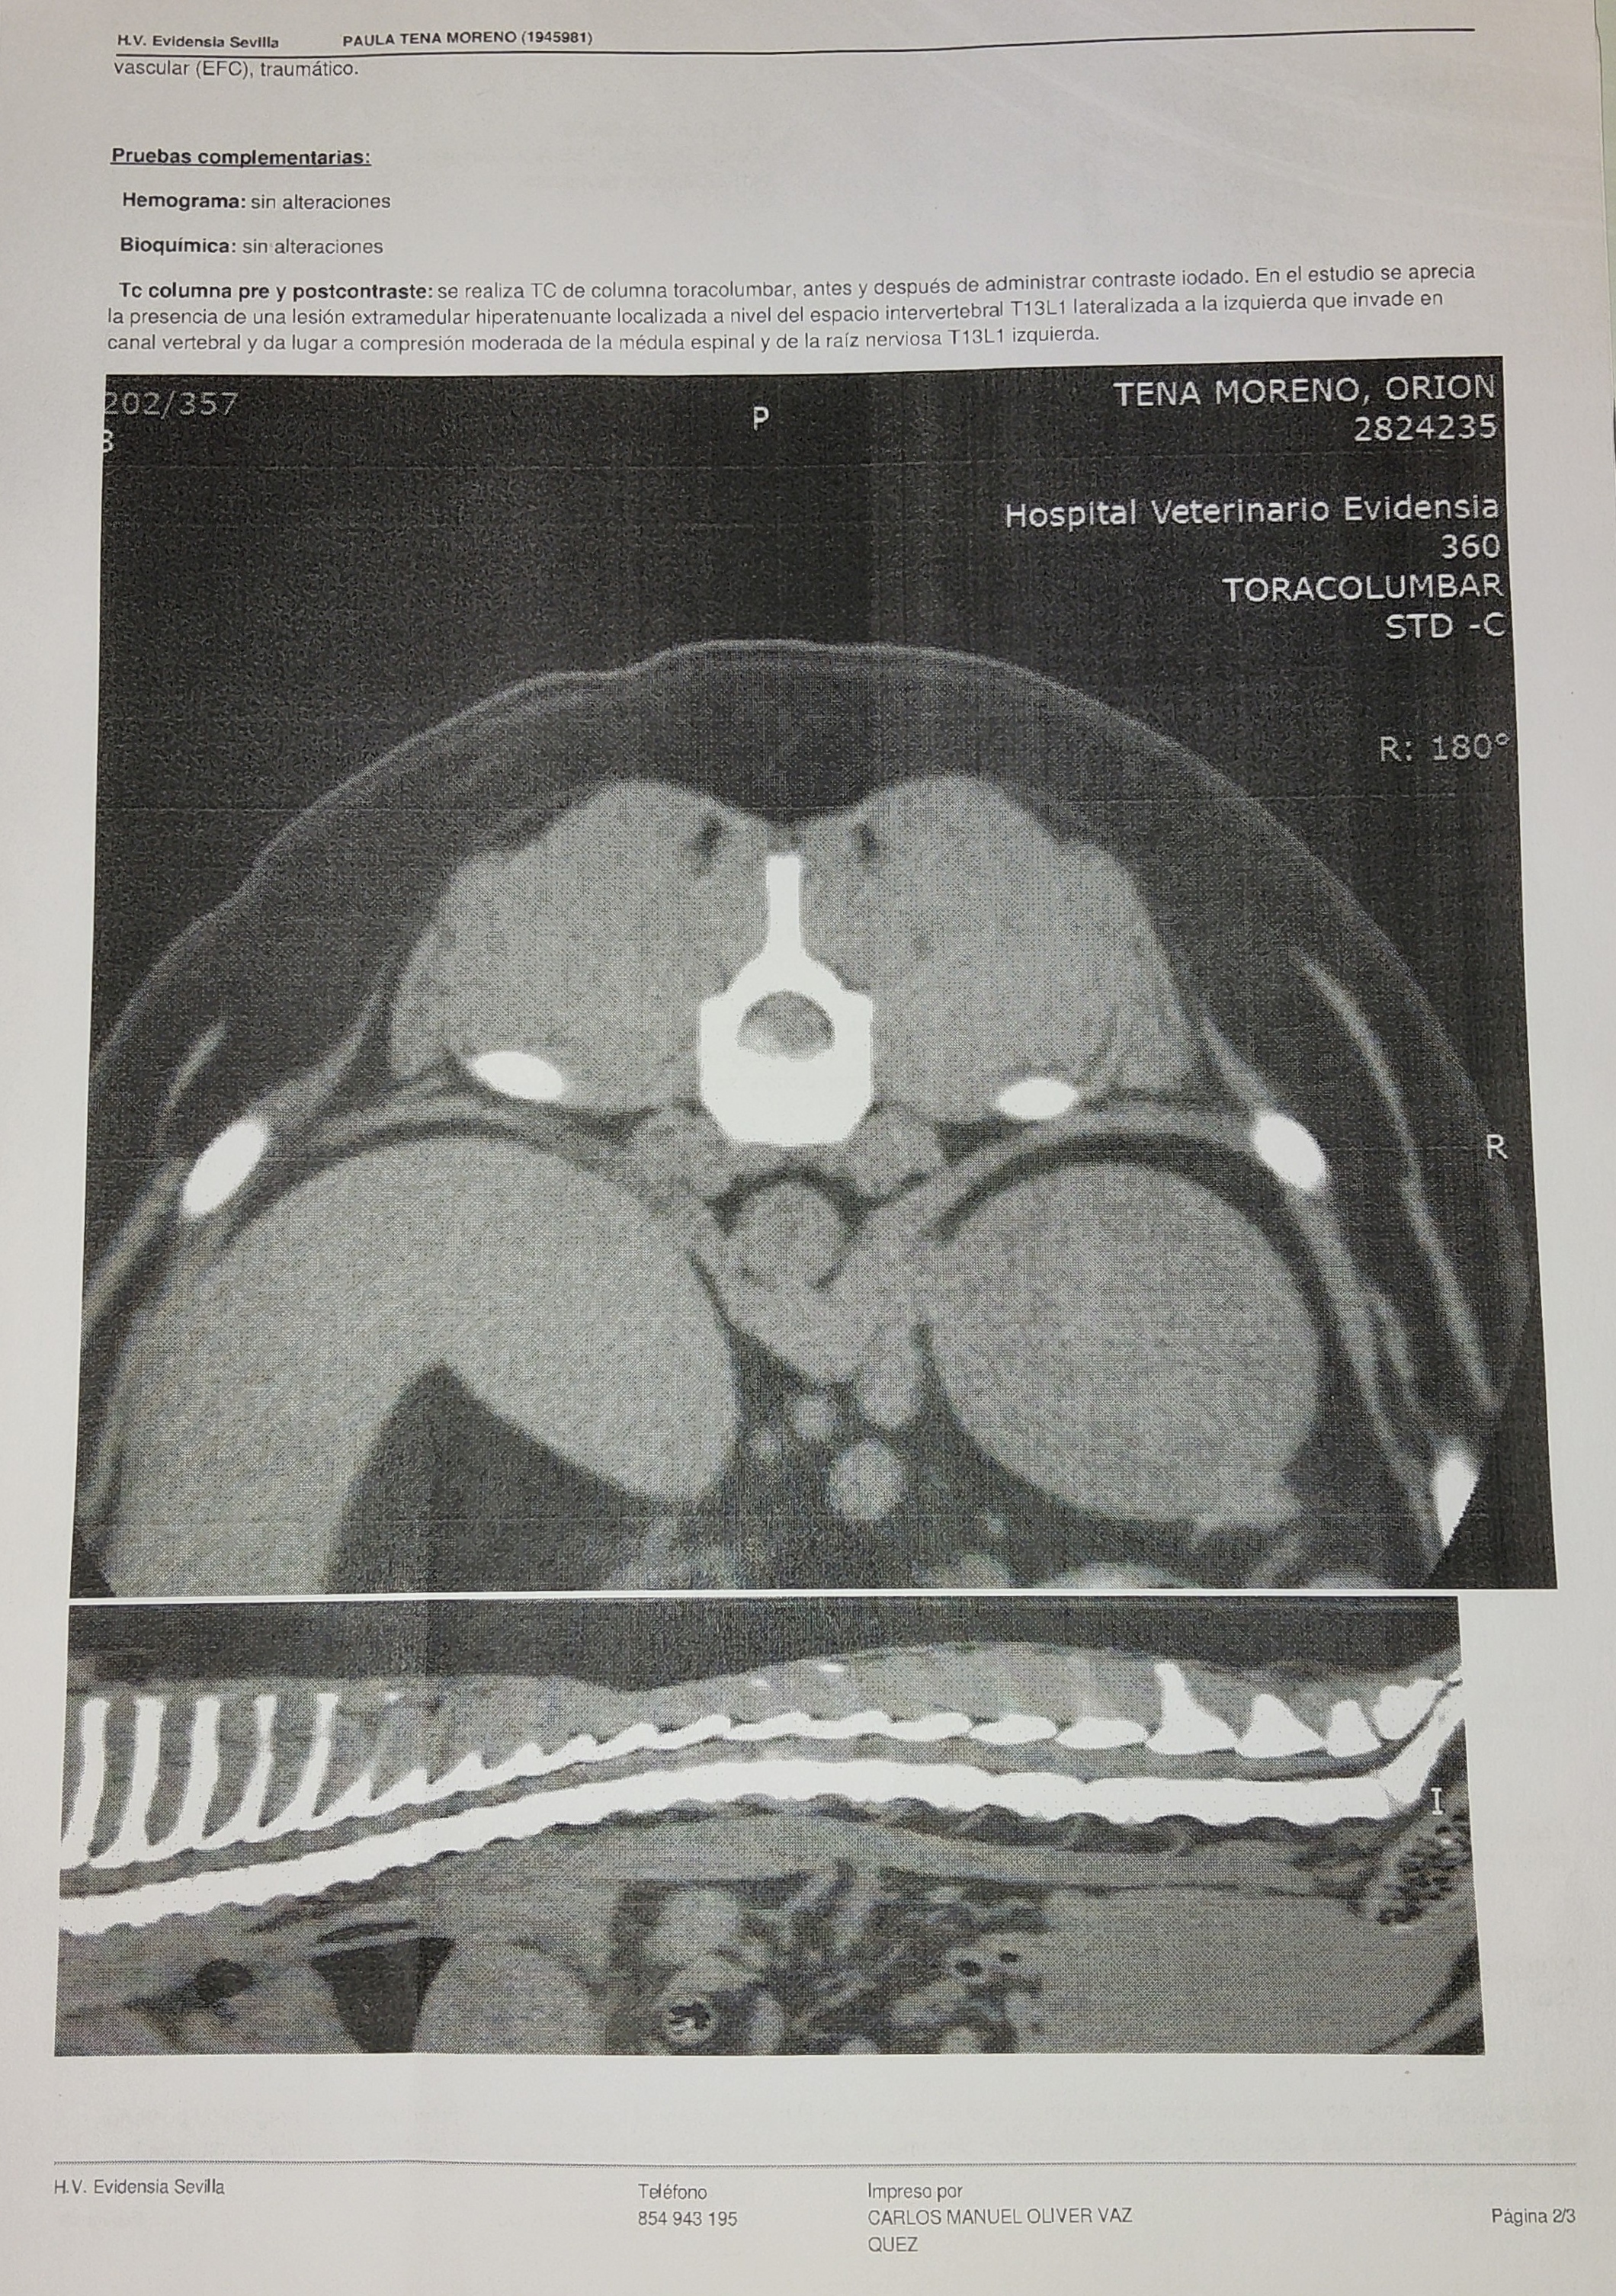

se le realizó un TAC cuyo diagnóstico es " Lesión extra medular hiperatenuante localizada a nivel del espacio intervertebral T13L1 lateralizada a la izquierda que invade el canal vertebral y da lugar a compresión moderada de la médula espinal y de la raíz nerviosa T13L1 izquierda"